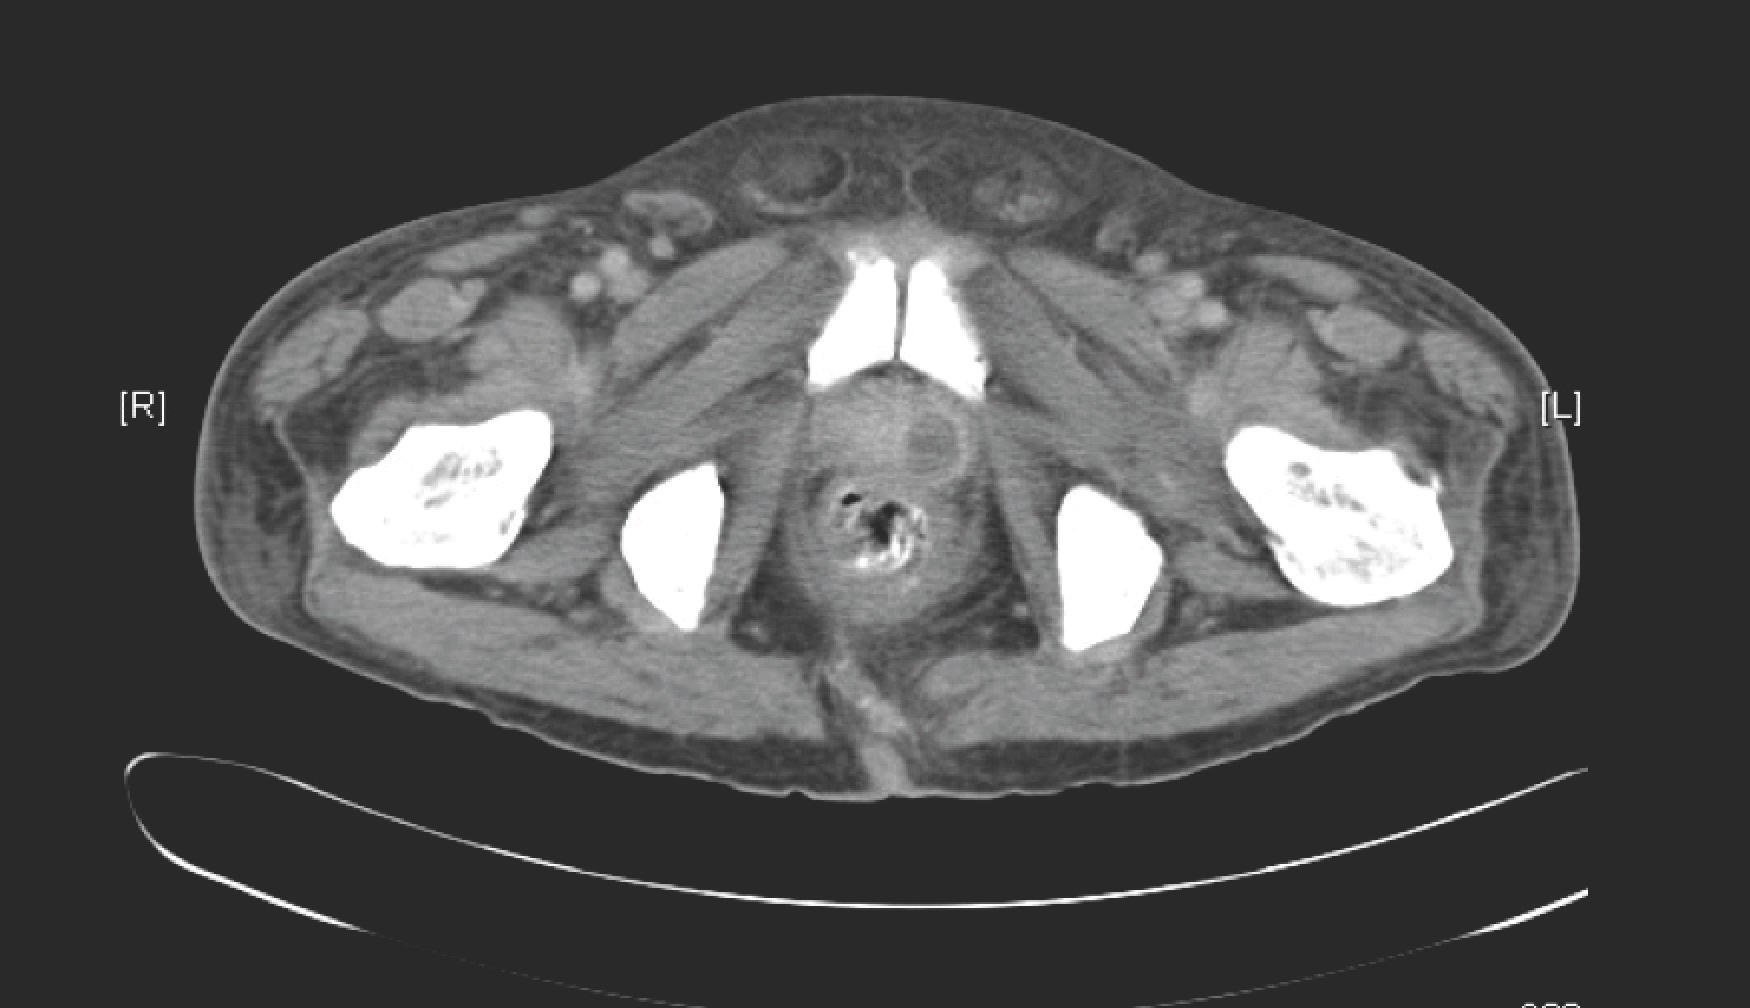

A middle-aged man presented with fever and dysuria for 5 days. He worked as a gardener at a large private housing estate, and suffered from both hypertension and type 2 diabetes mellitus. A CT pelvis was performed, with a representative image shown below.

The CT showed a hypodense lesion in the left lobe of the prostate, and in this clinical context, represents a prostatic abscess. Given the site of infection and the various risk factors – diabetes mellitus and contact with soil (gardener) – the most likely bacterial aetiology is Burkholderia pseudomallei, the organism that causes melioidosis. I will attempt to discuss melioidosis in a separate post.